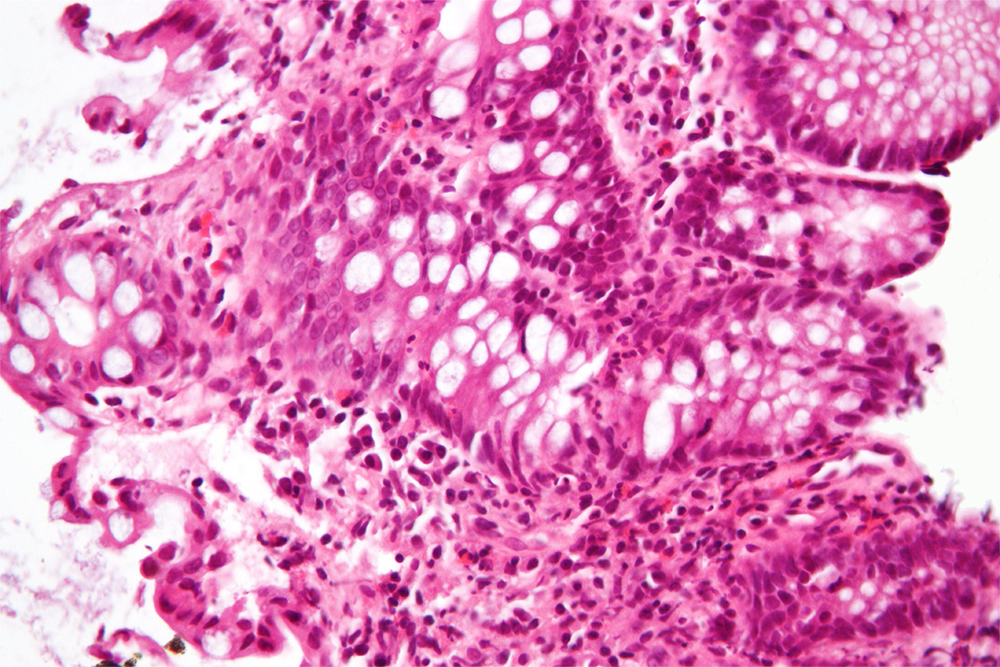

Whole-Genome Sequencing of African-Americans Implicates Differential Genetic Architecture in Inflammatory Bowel Disease,” published February 17 in the American Journal for Human Genetics, researches inflammatory bowel disease (IBD) and Crohn’s disease in more than 3,000 Americans of African descent. IBD patients made up 1,774 members of the group, while the control group numbered 1,644 individuals without IBD.

The group’s work hopes to build a better understanding of potential population divergence and genetic risk of specific complex diseases like IBD — as well as identify any possible corresponding evolution of susceptibility and origins of health disparities.

To achieve this, the research group set out to further resolve the genetic architecture of inflammatory bowel disease — and also to better define the differential genetic structure of the disease across divergent ancestries. The team notes that their resulting analyses “include many alleles that were not previously examined, in a population that remains very significantly understudied.”